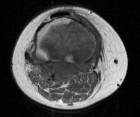

13 yo male with several months of right shin pain. No history of trauma. He describes the pain as sharp and stabbing and is now secondarily unable to bear weight. He complains of decreased appetite and pain at night.

PE: RLE: Palpable, tender mass with associated erythema and edema at proximal, medial calf. Pain with flexion greater than 90 degrees at the knee. Achieves full extension. NVI w/o LAN

WBC11.3, sed rate of 26, and CRP of 10.4